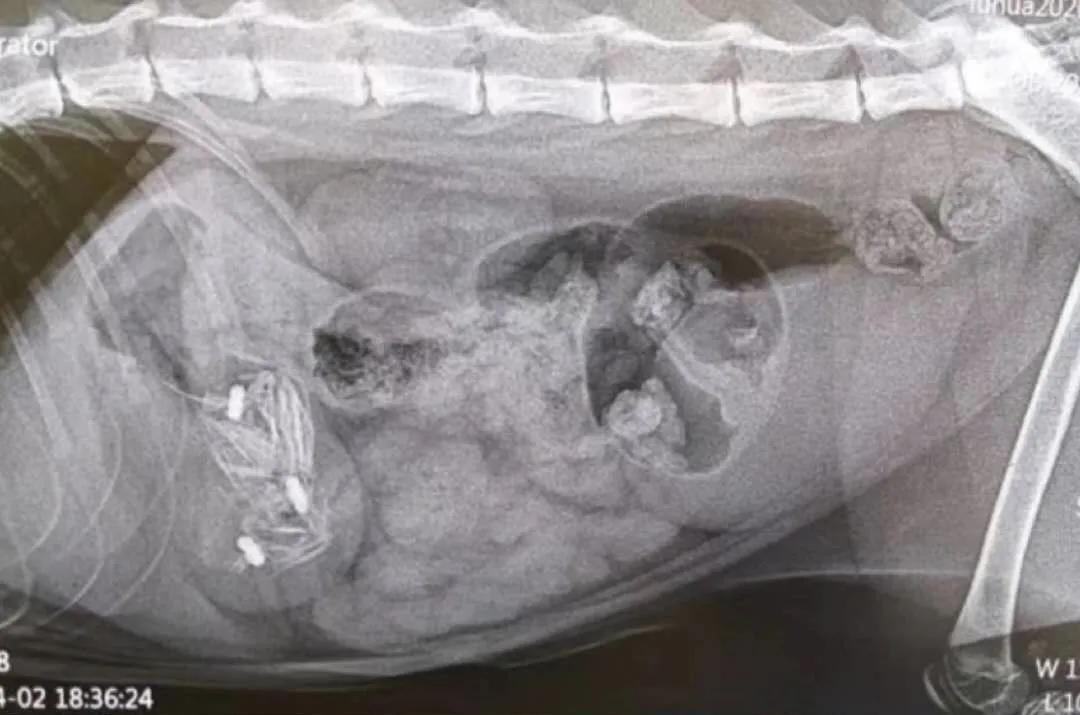

今天不知道怎么回事,三只猫吞异物来做内视镜。

一只吞订书针和橡皮筋,一只吞玩具,还有这只肚子里全是钢丝球。